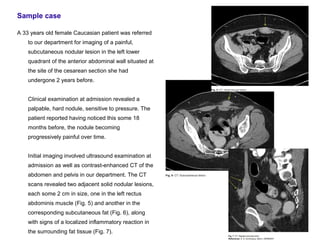

A 33 years old female Caucasian patient was referred

to our department for imaging of a painful,

subcutaneous nodular lesion in the left lower

quadrant of the anterior abdominal wall situated at

the site of the cesarean section she had

undergone 2 years before.

Clinical examination at admission revealed a

palpable, hard nodule, sensitive to pressure. The

patient reported having noticed this some 18

months before, the nodule becoming

progressively painful over time.

Initial imaging involved ultrasound examination at

admission as well as contrast-enhanced CT of the

abdomen and pelvis in our department. The CT

scans revealed two adjacent solid nodular lesions,

each some 2 cm in size, one in the left rectus

abdominis muscle (Fig. 5) and another in the

corresponding subcutaneous fat (Fig. 6), along

with signs of a localized inflammatory reaction in

the surrounding fat tissue (Fig. 7).